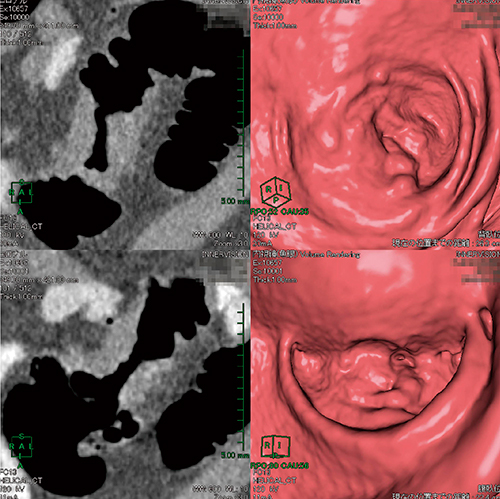

読影手順として,まず,仮想内視鏡像(以下,fly through)(図2)で直腸から盲腸まで観察し,反転して盲腸から直腸までを観察する。図1,2よりS状結腸に狭窄を認め,仮想内視鏡+multi planer reconstruction(MPR)画像(図3)にて病変と判断した。以前は注腸X線検査で静止画しか得られなかった注腸画像も,大腸CTで得られた画像をAZE VirtualPlace雷神で3D画像処理をすることにより,画像を任意の角度へ回転し,あらゆる方向から観察が可能である(図4)。fly through画像では,内視鏡で観察が難しい反転の画像も容易に表示することが可能である(図5)。撮影は2体位実施しているため画像の比較も容易であり(図6),診断に有用な画像処理が可能になる。また,レポート作成機能も搭載されており,容易にレポートを作成することができる。出力の書式はWord形式(図7,8)やPDF形式が用意されており,これらのファイルをDICOMに変換して画像として電子カルテに転送することも可能であるため,施設に合った方式を選択できる。

図3 仮想内視鏡+MPR画像 |

図5 仮想内視鏡像の反転表示 |